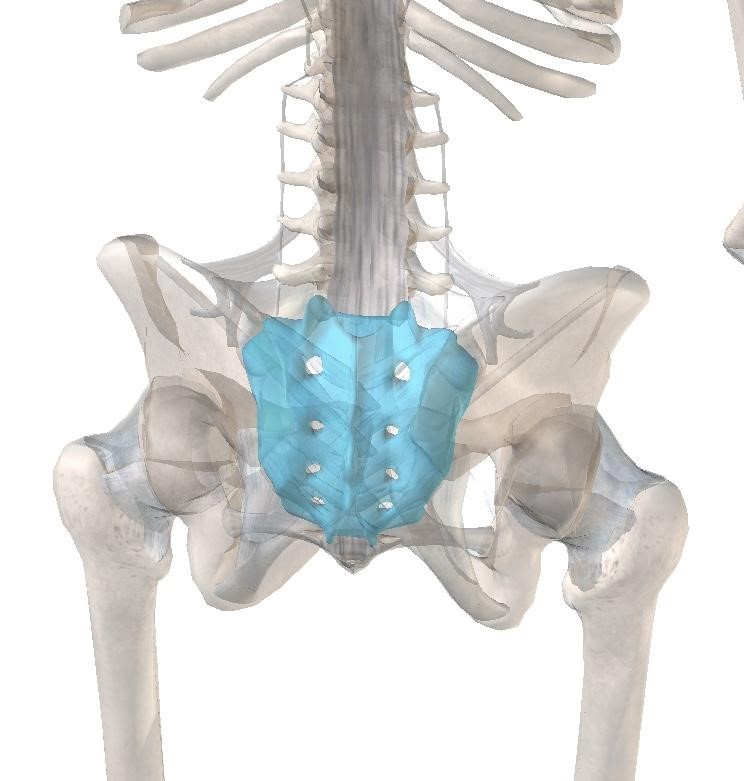

Stress Fracture Sacrum Running . Learn about the symptoms and how to prevent this common. sacral stress fractures, though uncommon, should be included prominently in the differential diagnosis for runners. manage sacral stress fracture with proper diagnosis and treatment. However, stress fractures rarely arise in the sacral bone. stress fractures occur more commonly in female runners and military workers. They most commonly appear after the runner increases the intensity of an activity or alters the manner in which an activity is performed. sacral stress fractures occur more easily in people with bones weakened by osteoporosis, osteopenia, or nutrition problems, including deficiencies in calcium and vitamin d. Low back pain is a common problem in active populations, but i rarely see runners with back pain—and when i do, it’s often a bone stress injury (bsi). stress fractures of the lower extremity are common injuries among individuals who participate in endurance,. sacral stress fractures are most commonly found in female distance runners, but also have been reported in other sports such as tennis, basketball, gymnastics, volleyball, and track and field. Patients typically report buttock pain, but also can report low back pain, groin pain, and muscle spasms. These fractures typically manifest unilaterally, affecting the bones of the lower limb. Sacral stress fractures can go undiagnosed for a long time due to similarities to other conditions, such as sciatica.

Stress Fracture Sacrum Running Sacral stress fractures can go undiagnosed for a long time due to similarities to other conditions, such as sciatica. Low back pain is a common problem in active populations, but i rarely see runners with back pain—and when i do, it’s often a bone stress injury (bsi). sacral stress fractures are most commonly found in female distance runners, but also have been reported in other sports such as tennis, basketball, gymnastics, volleyball, and track and field. stress fractures of the lower extremity are common injuries among individuals who participate in endurance,. Patients typically report buttock pain, but also can report low back pain, groin pain, and muscle spasms. However, stress fractures rarely arise in the sacral bone. sacral stress fractures, though uncommon, should be included prominently in the differential diagnosis for runners. These fractures typically manifest unilaterally, affecting the bones of the lower limb. Learn about the symptoms and how to prevent this common. stress fractures occur more commonly in female runners and military workers. They most commonly appear after the runner increases the intensity of an activity or alters the manner in which an activity is performed. manage sacral stress fracture with proper diagnosis and treatment. sacral stress fractures occur more easily in people with bones weakened by osteoporosis, osteopenia, or nutrition problems, including deficiencies in calcium and vitamin d. Sacral stress fractures can go undiagnosed for a long time due to similarities to other conditions, such as sciatica.